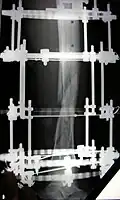

Наложенный аппарат Илизарова на правую голень (фиксация большеберцовой и малоберцовой костей)

Аппарат изготовляется из специальной нержавеющей стали или титана и состоит из 2 и более колец и 2-3 стяжных стержней, на концы которых навинчены гайка и контргайка. Аппарат стерилизуется; через кость при помощи специальной медицинской дрели проводятся в перекрещивающих направлениях с учётом топографии сосудов и нервов спицы, которые затем фиксируются к кольцам. Перед проведением спицы соответствующие участки кожи смещаются на 0,5–1 см. После проведения спиц на их концы надеваются пропитанные спиртом марлевые салфетки, которые прижимаются пробками. Соединяющие кольца стержни устанавливаются параллельно друг другу. Репозиция обломков костей производится затягиванием гаек и контргаек. Вслед за наложением аппарата осуществляется контрольная рентгенография, позволяющая корригировать положение обломков. Стабильность фиксации поддерживается равномерным подвинчиванием гаек на ¼ оборота каждого стержня до 2 мм каждые 5–7 дней[2].

Процедура лечения открытого перелома большой и малой берцовой костей аппаратом Илизарова. Фотографии и рентгенограммы одного и того же пациента в течение курса лечения. Снимки 2 — 6 сделаны через четыре недели после перелома (две недели после наложения аппарата).